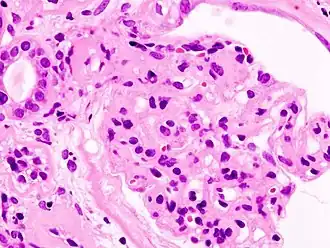

Нефроти́ческий синдро́м — состояние, характеризующееся генерализованными отёками, массивной протеинурией (выше 50 мг*кг/сут или выше 3,5 г/сутки), гипопротеинемией и гипоальбуминемией (менее 20 г/л), гиперлипидемией (холестерин выше 6,5 ммоль/л). Термин предложен Е. М. Тареевым в 1923 году.

Характерен для поражения клубочкового аппарата почек.

Гистологическая классификация

| Болезнь минимальных изменений | Фокальный сегментарный гломерулосклероз | Мембранозная нефропатия | Мембранопролиферативный гломерулонефрит | ||||||||||||||||||||||||||||||||||||||